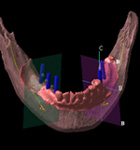

CTにて撮影したデータを、3次元画像解析システムにより、患者さんの神経や骨の状態を細部まで分析します。

模型確認

必要に応じて患者さんの3次元顎体模型を作り、顎骨の形を事前に把握します。